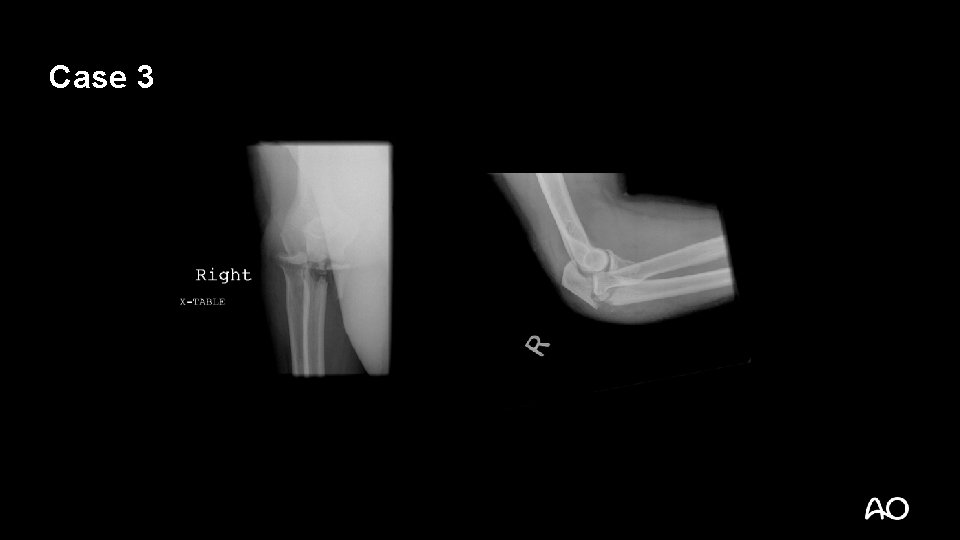

Case 3

Monteggia variant fracture dislocation • Most often posterior dislocations with associated proximal ulnar/olecranon fractures • May have associated radial head fractures • Principles are similar to treatment of standard Monteggia injuries of forearm

Monteggia variant—tactic • Principle: anatomical reduction of ulna is critical for maintenance of radial head reduction • Extensile posterior approach: • Can get to radial head for repair if necessary